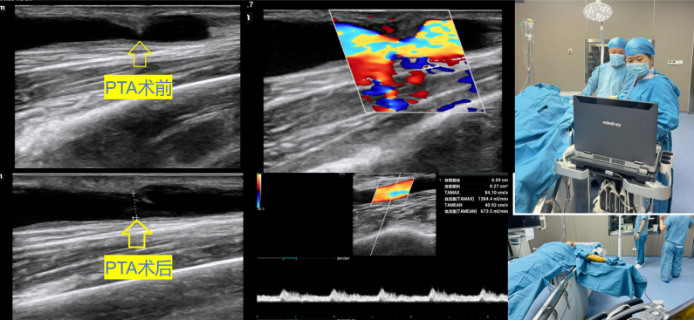

西咸院区肾内科进一步治疗,闫晓辉副主任医师积极安排患者完善相关检查,超声医学中心韦爱华副主任医师认真为患者进行血管评估,发现由于自体动静脉内瘘静脉侧局段狭窄导致该患者血流量明显下降。闫晓辉副主任医师与患者及家属充分沟通,决定为患者进行超声引导下动静脉内瘘狭窄球囊扩张术。

在超声医学中心刘莉主任和穆靓副主任的安排下,韦爱华副主任医师利用便携式超声诊断仪床旁配合闫晓辉副主任医师,为该患者顺利进行自体动静脉内瘘狭窄球囊扩张术。术后恢复良好,狭窄处的管径从1.3mm增宽到4.0mm,进行穿刺内瘘血液透析治疗血流量充足,泵控血流量达250ml/min。

PTA手术是处理动静脉内瘘狭窄、闭塞的一种治疗方法,具有微创、安全、并发症少、重复性高等优势,不仅能够保护通路血管的连续性和完整性,并且最大限度保存患者有限的血管资源,降低了外科手术并发症发生的风险,因此成为内瘘狭窄、闭塞的一线治疗方法。与传统造影相比,PTA手术可实时动态观察导丝、球囊导管与血管之间的关系,动态监测血流动力学参数变化以了解内瘘功能,准确定位病变部位,根据血管直径选择合适球囊,避免造影剂不良反应的发生等。